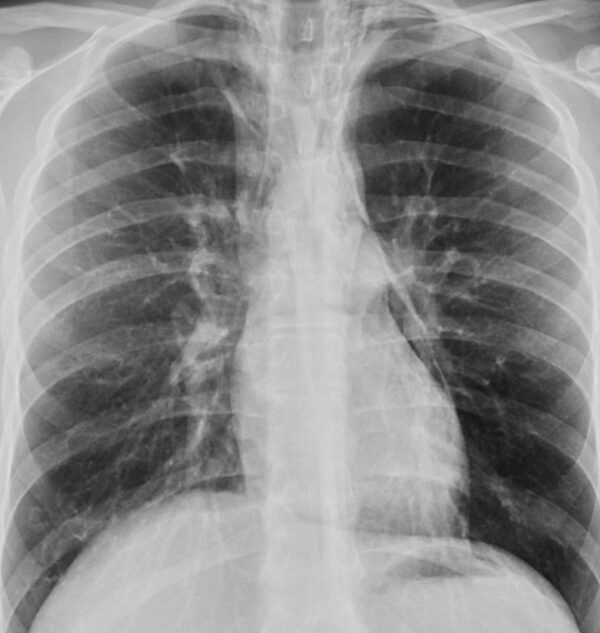

Case 37

https://radiopaedia.org/cases/pneumomediastinum-13

X-RAY

CHEST